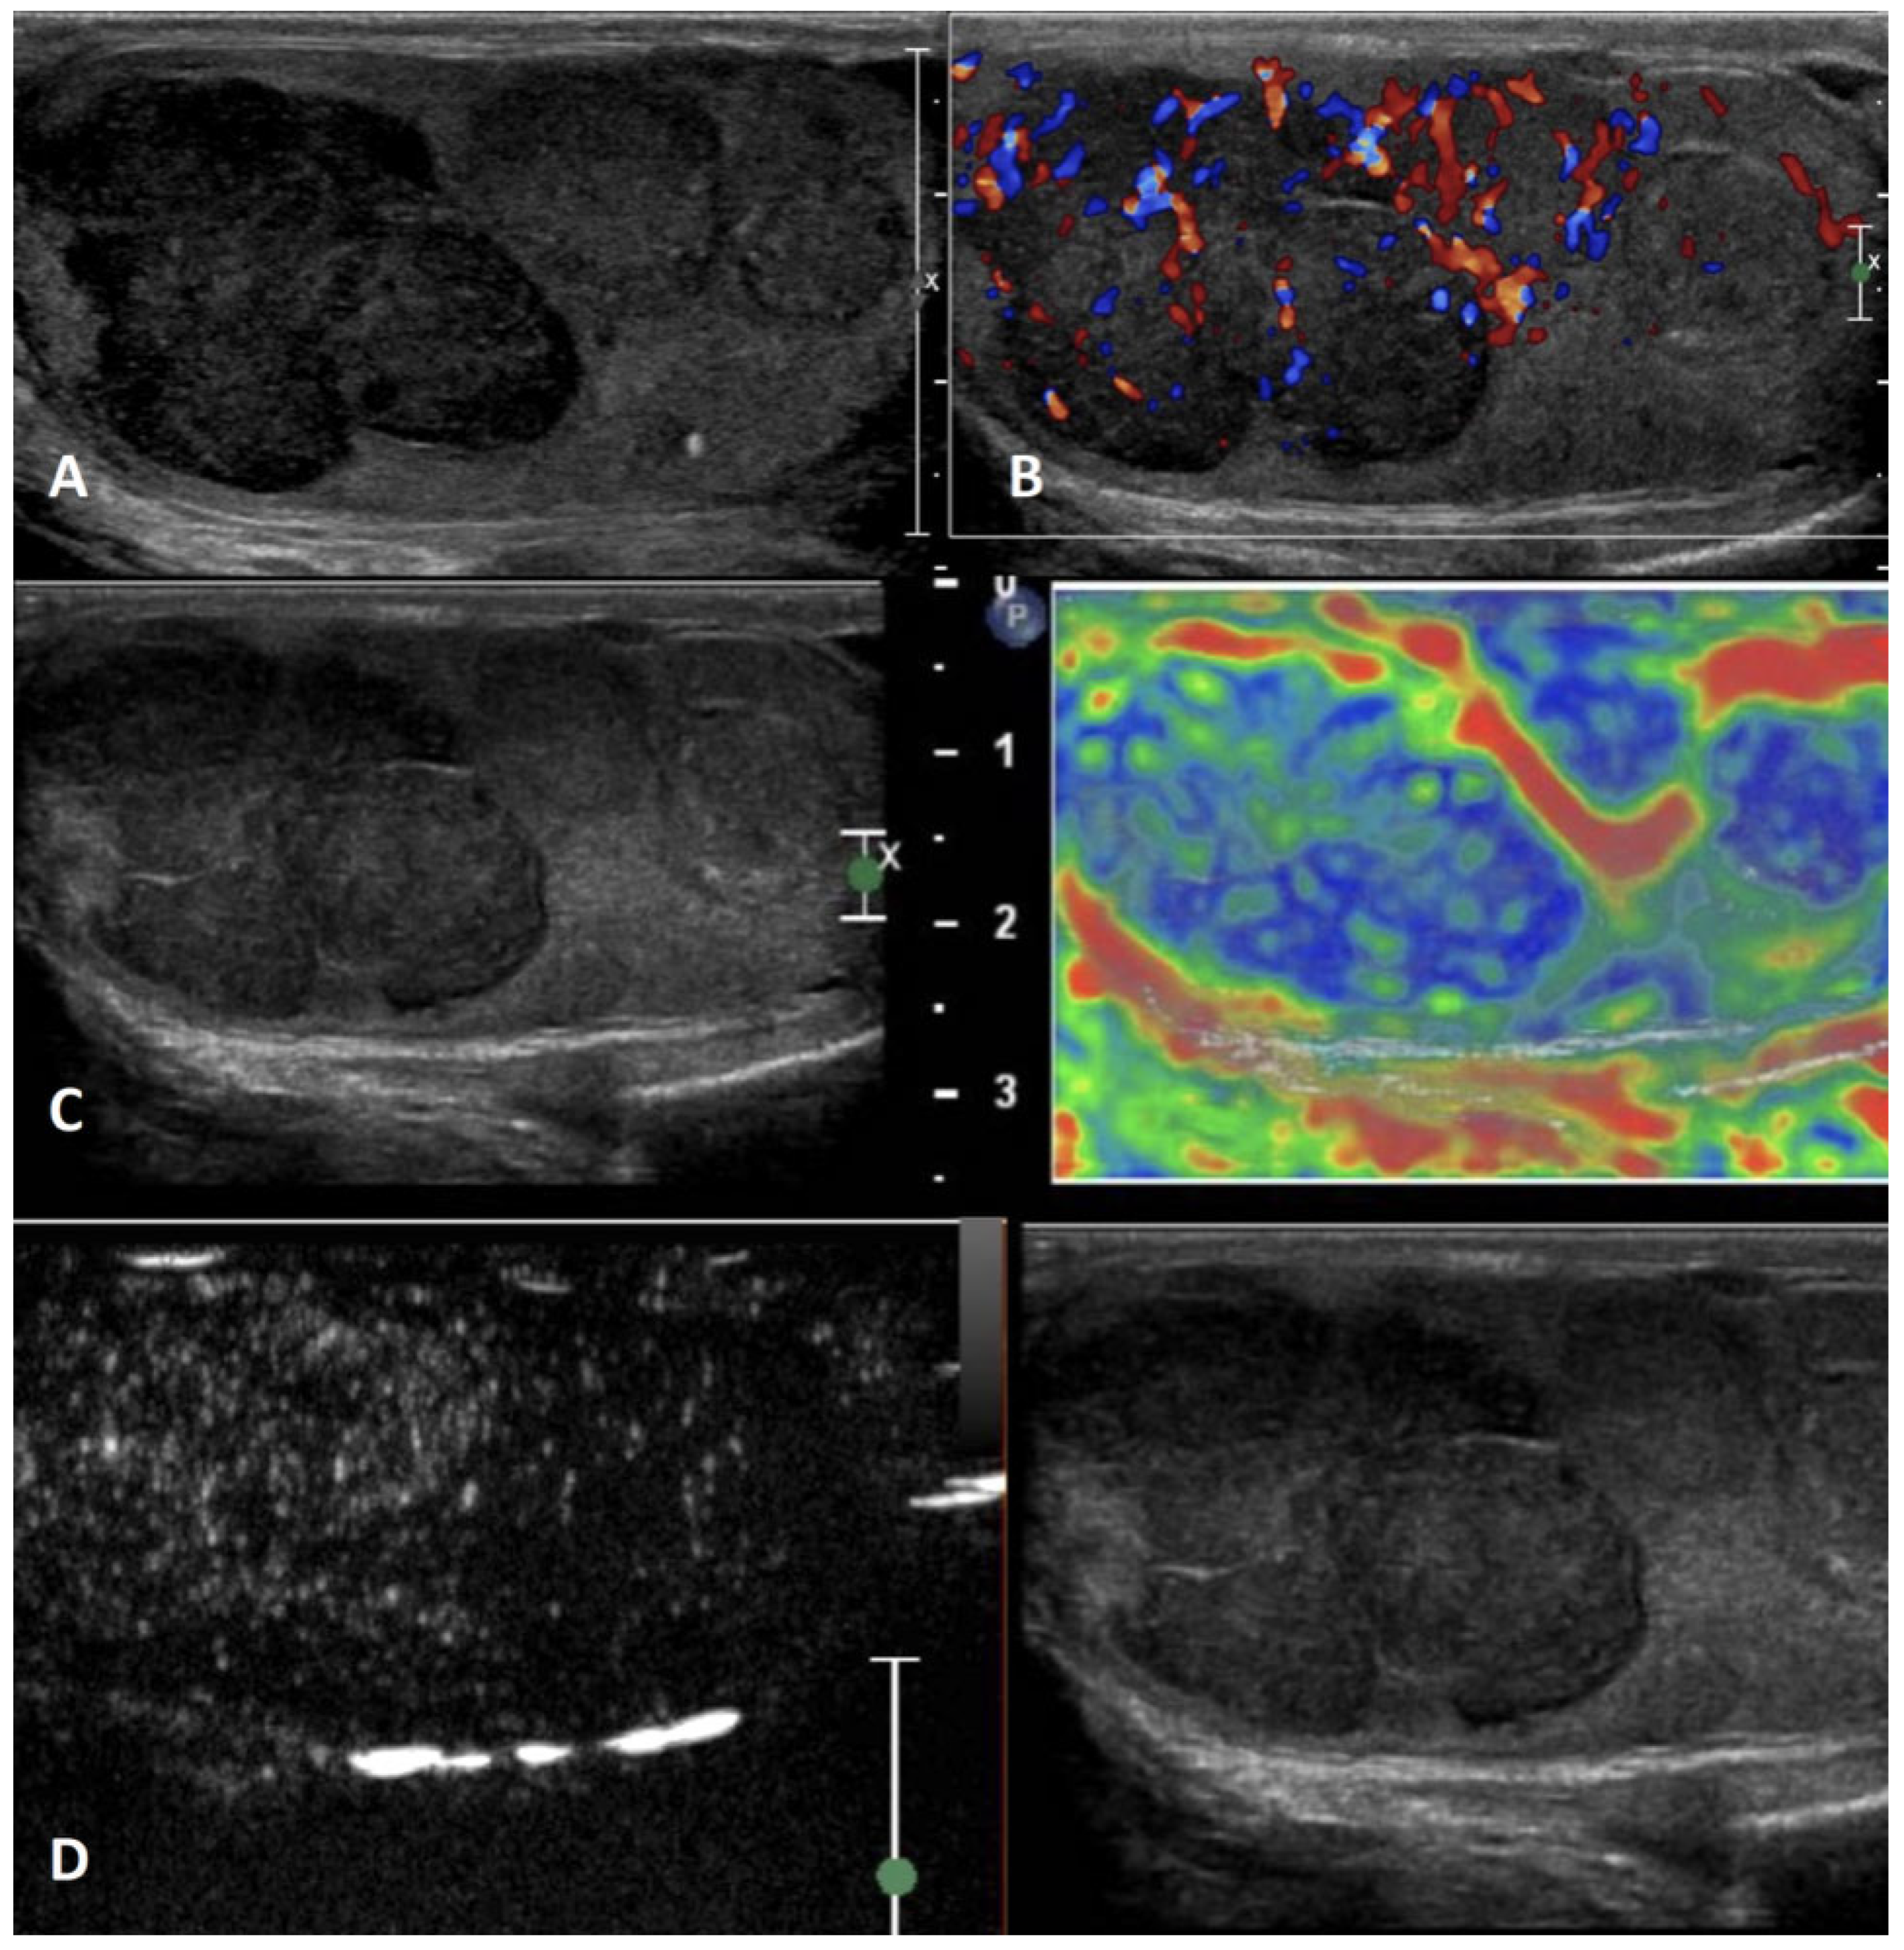

5.4.1. Lymphoma

| Lymphoma | Testicular swelling, pain, and specific lymphoma symptoms; affects men older than 50 years, palpable firm testicular mass | Negative | Hypoechoic lesions with diffuse infiltration or multifocal hypoechoic lesions of various size | Hypervascularized with linear non-branching pattern | Hyperenhanced | Hard lesions with low/absent elastic strain |

5.4.2. Primary Testicular Leukemia

| Leukemia | More frequent in children and young patients; it can be asymptomatic | Negative | Infiltrating pattern with irregular hypoechoic longitudinal striae/focal pattern with irregular hypoechoic nodules | Hypervascularized | Inhomogeneously hyperenhanced | Hard lesions with low/absent elastic strain |